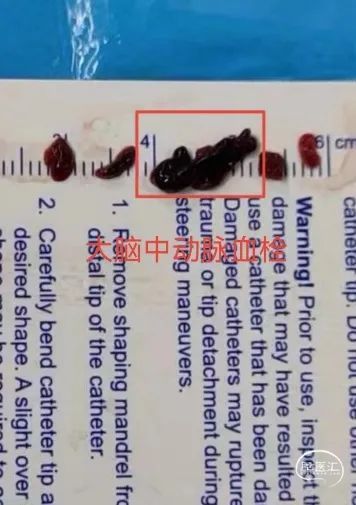

2. 血栓性质:可能为红细胞含量较高的血栓。头颅CT影像大脑中动脉走行区高密度征。

第四步处置:抽吸取栓

抽吸取栓优点

操作更加简单,快速、安全

栓塞性病变更适合抽吸取栓

血栓性质倾向于红色血栓或混合血栓

抽吸取栓成功率高,血栓逃逸风险小